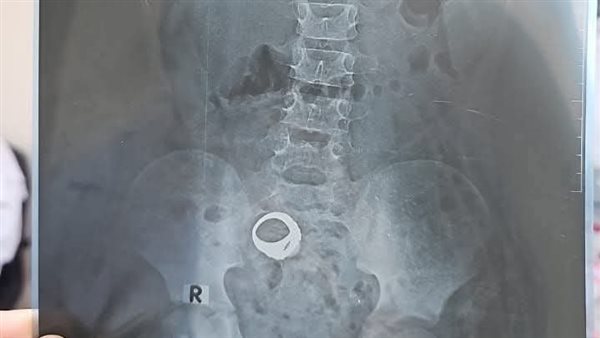

وأكدت إدارة المستشفى أنه ردا على ما تم تداوله على بعض صفحات التواصل الاجتماعي بشأن عودة الطفل معاذ عمار ياسر إلى المستشفى نحيطكم علما بأن الحالة من قرية واقد، وتم الكشف عليها، وتم طلب الأشعة اللازمة.

وتابع البيان: وقامت الأم بعمل الأشعة وتركتها ولم تقم بالذهاب مرة أخرى للعياده لمتابعة الحالة، ومن هنا نحيطكم علما أنه تم التواصل مع بعض الأهالى بقرية واقد للتعرف على الحالة، ونحيطكم علمًا بأن هذه الحالات ليست حالات طارئة ويمكن متابعتها بالعيادة الخارجية بالمستشفى.

وأكد رواد ومستخدمو مواقع التواصل الاجتماعي عبر موقع "فيسبوك" أنه بعد خروج الطفل من المستشفى أظهرت الأشعة وجود خاتم داخل بطن الطفل، لذلك انتشرت الدعوات العاجلة لأي شخص يعرف الطفل أو أسرته أن يتواصل فورًا مع المستشفى أو يذهبوا به سريعًا.